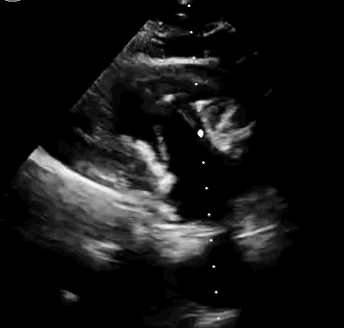

本次臨床前研究經(jīng)右側(cè)頸靜脈置入LuX-Valve Plus輸送系統(tǒng)可調(diào)彎鞘管,在DSA及超聲引導(dǎo)下將人工三尖瓣瓣膜植入到原有三尖瓣位置,利用獨(dú)特的錨定技術(shù)將人工瓣膜支架可靠固定在預(yù)定的位置。